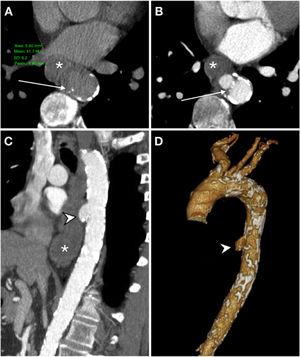

Primary aorto-oesophageal fistula in a 67-year-old male with haematemesis, profuse sweating, skin pallor and hypotension. Baseline computed tomography (A) showed oesophageal dilatation with intraluminal content of high attenuation in relation to a blood component (*) and displacement of intimal calcifications indicating rupture of an atheromatous plaque with an entrance (arrow). The arterial phase on the axial plane (B), sagittal reconstruction (C) and volumetric reconstruction (D) showed calcifications in the wall of the descending aorta and saccular dilatation (arrow tip) in contact with the oesophageal wall with no fat plane achieving separation. These findings suggested a penetrating ulcer. Despite the absence of extravasation of intravenous contrast, the presence of an aortoenteric fistula was confirmed in surgery.